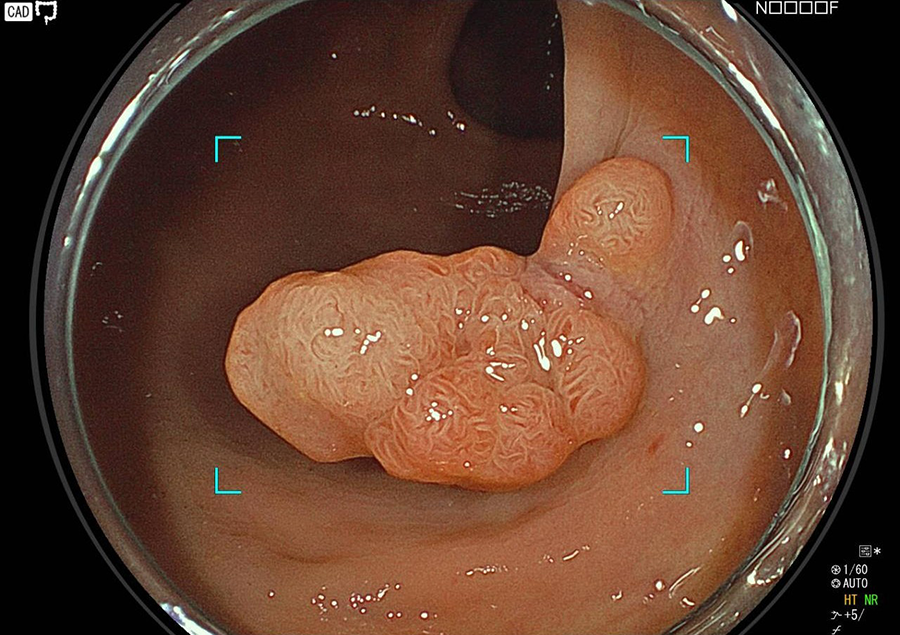

検査の様子

そこで当院では大腸カメラ検査時にポリープや早期がんが発見された場合は、可能な限り積極的にその場で切除しております。

一般的に大腸ポリープのうち、約5%が早期がんといわれ、また良性のポリープもがんの発生母地になるといわれています。

近年、大腸がんが急速に増加していますが、がんの芽となるポリープ(腺腫)、一部の早期がんは、大腸カメラによる内視鏡治療で完治させることが可能です。